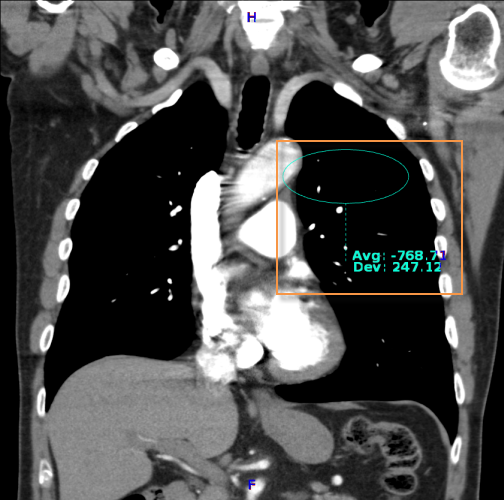

A Hounsfield annotációs eszköz létrehoz egy vizsgált területet, és kiszámítja annak átlagos pixelértékét és szórását.

Hounsfield-érték méréséhez:

Válassza a Hounsfield-érték  ikont

ikont

Kattintson az ROI-re

Húzza az egeret a terület meghatározásához

Engedje el az egérgombot

A képre rajzolt alapértelmezett vizsgált terület egy teljes kör. ROI átméretezése során a teljes kört a sarkakon található fogópontokkal tarthatja fenn

A középső megfogási ponttal  mozgathatja az ROI-t a képen, a többivel pedig nyújthatja vagy keskenyítheti.

mozgathatja az ROI-t a képen, a többivel pedig nyújthatja vagy keskenyítheti.